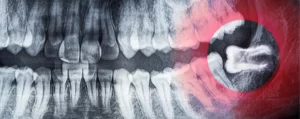

Radiografía panorámica dental: el primer paso antes de tu ortodoncia

Por Alfonso Gálvez Vargas

Iniciar un tratamiento de ortodoncia, especialmente uno tan avanzado como la ortodoncia invisible, implica mucho más que solo colocar alineadores.  Uno de los pasos fundamentales, y que marca la diferencia…

radiografía panorámica dental